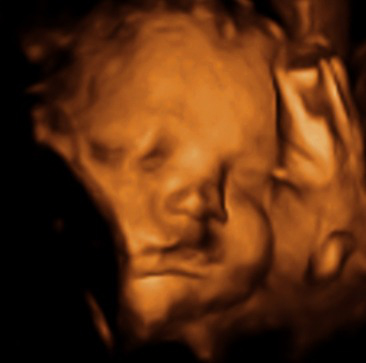

Ecografías con semanas de 35 de embarazo

¿Sabes que ahora también puedes hacerte una ecografía 5D, con una mejor definición de tu bebé y en la que el color de la piel del bebé es rosado en lugar de sepia? La ecografías que te mostramos a continuación son las diagnósticas ya conocidas en 3D:

Ecografía semana 35: cara y moflete de bebé. El ecógrafo nos ofrece esta imagen de la cara (se marca incluso el moflete) de un feto de 35 semanas de gestación.